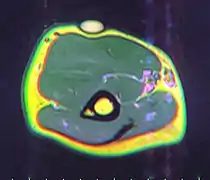

A physical exam is typically the easiest way to diagnose it. Rarely, a tissue biopsy or imaging may be required. The imaging modality of choice is magnetic resonance imaging (MRI) because it has superior sensitivity of distinguishing it from liposarcoma as well as mapping the surrounding anatomy.[22]

The presence of multiple lipomas, lipomatosis, is more commonly encountered in men. Some superficial lipomas can extend into deep fascia and may complicate excision. Liposarcoma is found in 1% of lipomas and is more likely to occur in lesions of the lower extremities, shoulders, and retroperitoneal areas. Other risk factors for liposarcoma include large size (>5 cm), associated with calcification, rapid growth, and/or invasion into nearby structures or through fascia into muscle tissue.[39]